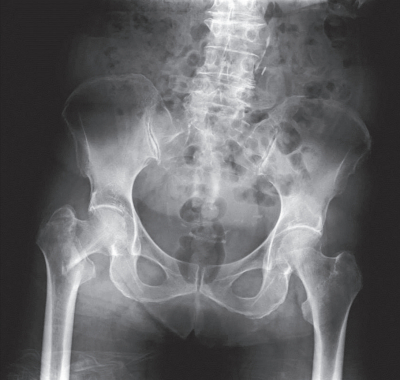

意識は清明。心拍数 92/分、整。血圧 170/100 mmHg。SpO₂ 100 %(リザーバー付マスク 10 L/分 酸素投与下)。右股関節を動かすと痛がる。右下腿に腫脹を認めず圧痛もはっきりしない。上肢の筋力低下を認めない。四肢の腱反射は正常である。感覚の左右差はない。骨盤エックス線写真を別に示す。

最も考えられるのはどれか。

e. 大腿骨近位部骨折